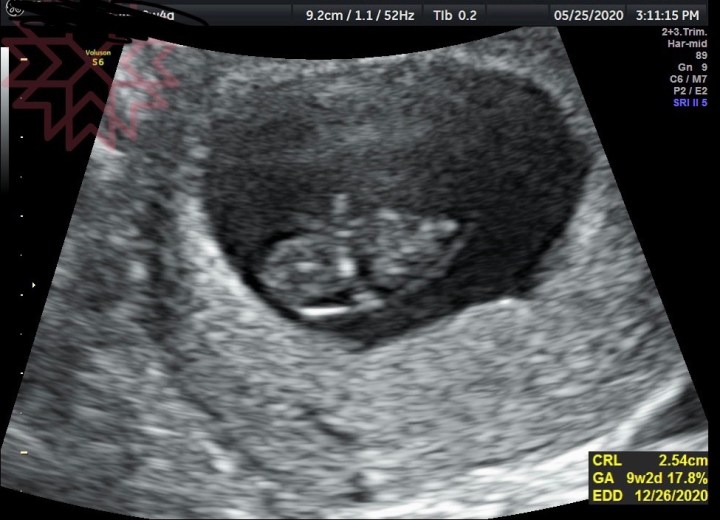

跳號跳到了我們,進診間後按往例跟林思宏院長簡短地打完招呼、躺上診療台準備進行超音波檢測,但這次當探照儀覆上我的肚子時,連我都感覺到情況似乎有點不對。那本該有閃爍的心跳,這次怎麼好像看不到?原本希望是我自己多心,但當林思宏院長轉開心跳聲的儀器時,我聽到了最令人孤寂、最心痛、最失落的聲音…無聲。

沒有心跳了,我的二寶離開了。

回到家後,請老公幫我顧一下蛋黃,我一個人在房間崩潰大哭,雖然知道地球上每一次的懷孕,大概都有1/5的人會經歷早期的流產,但怎麼也沒想過自己就會是那一個人。腦中不斷重複播放當天下午超音波螢幕上的畫面,以及那空蕩蕩的聲音。我很少在老公面前崩潰大哭,那天,真的無法再佯裝堅強了。

原本以為妳是我今年最棒的生日禮物,預產期還是12月24日,多喜慶。其實也確實是份禮物呀,只是你不能陪我到最後。

短短一個多月的旅程,像場夢一樣。但我更希望昨天是場夢,螢幕上空蕩蕩的心跳顯示、醫生的表情、他說出口的話等,都是假的,我等下醒來就沒事了。

那個仰角30度的視角,看到了絕望的畫面,聽到了最空蕩的聲音。漆黑死寂。